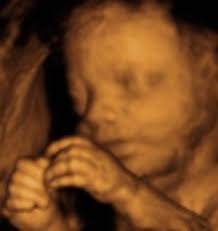

3d Image Of Baby At 27 Weeks Images Poster

3d Image Of Baby At 27 Weeks Images Poster from i.pinimg.com